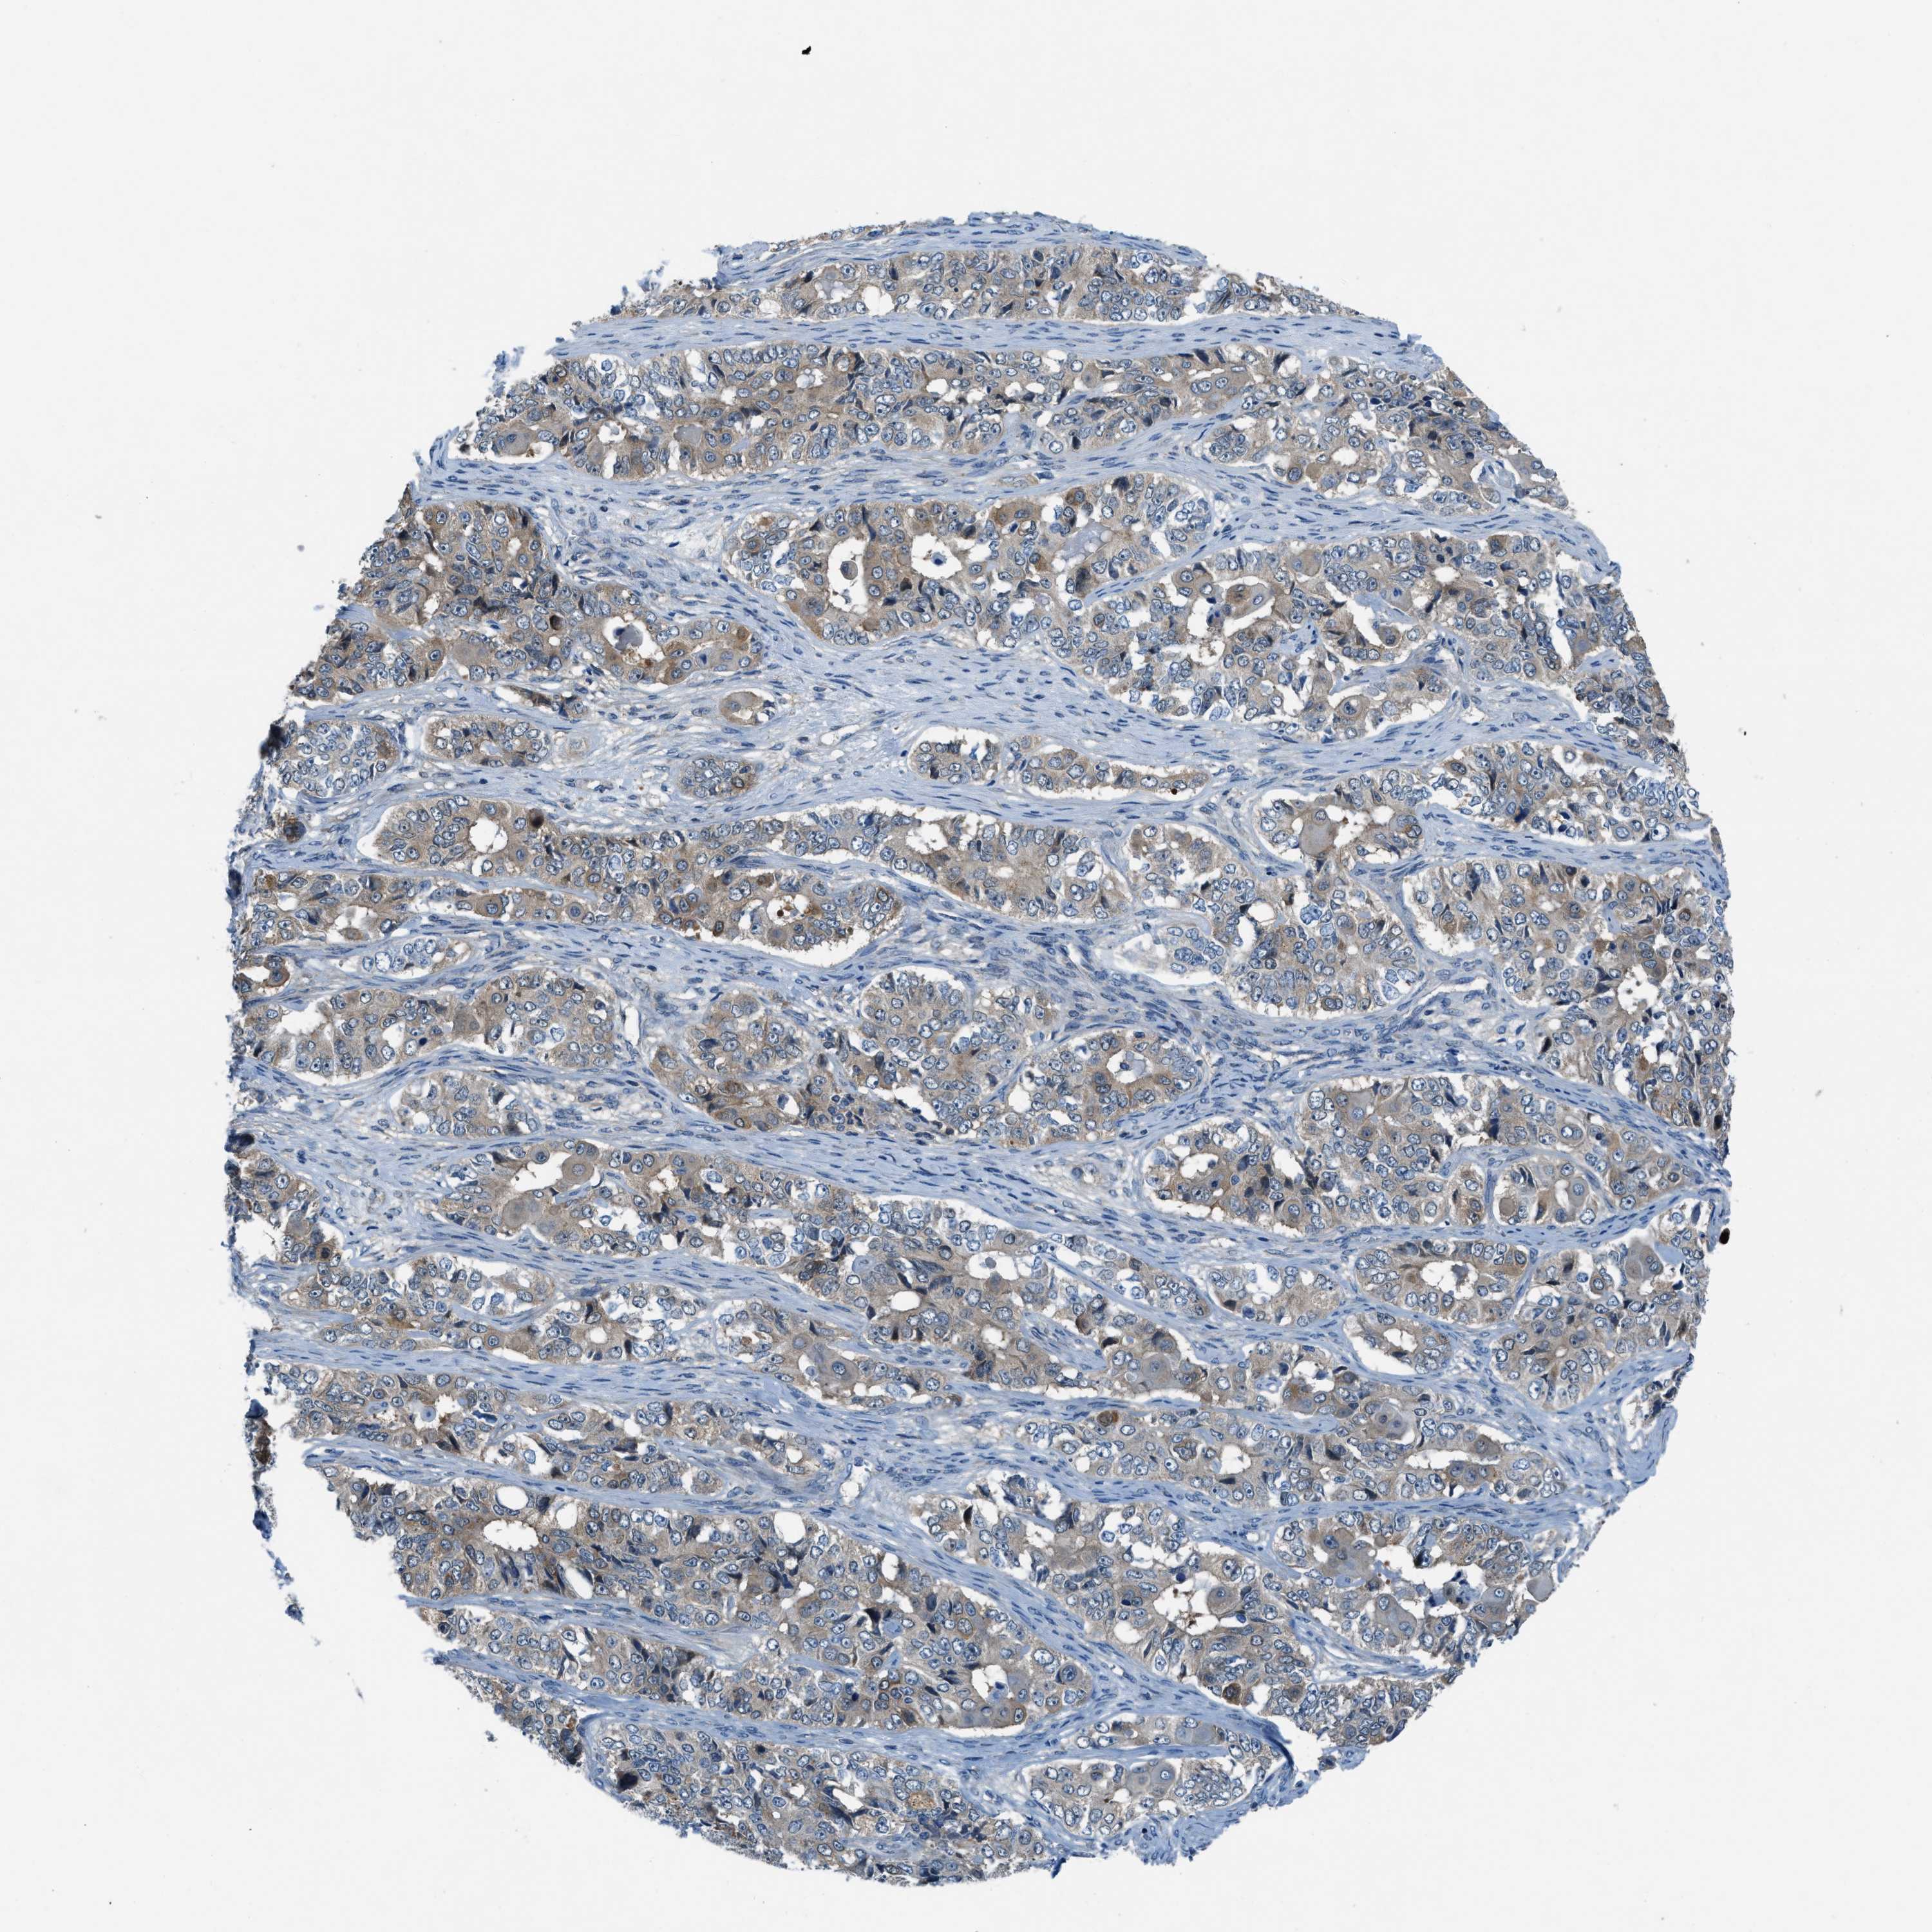

OVARIAN CANCER - Protein expressioni

A mouse-over function shows sample information and annotation data. Click on an image to view it in a full screen mode. Samples can be filtered based on level of antibody staining by selecting one or several of the following categories: high, medium, low and not detected. The assay and annotation is described here.

Note that samples used for immunohistochemistry by the Human Protein Atlas do not correspond to samples in the TCGA dataset.

Antibody stainingi

Antibody staining in the annotated cell types in the current human tissue is reported as not detected, low, medium, or high, based on conventional immunohistochemistry profiling in selected tissues. This score is based on the combination of the staining intensity and fraction of stained cells.

Each image is clickable and will lead to virtual microscopy that enables deeper exploration of all samples and also displays staining intensity scores, fraction scores and subcellular localization as well as patient and tissue information for each sample.

Antibody HPA016649

Antibody HPA018152

Cystadenocarcinoma, serous, NOS

Carcinoma, endometroid

Cystadenocarcinoma, mucinous, NOS

Carcinoma, NOS